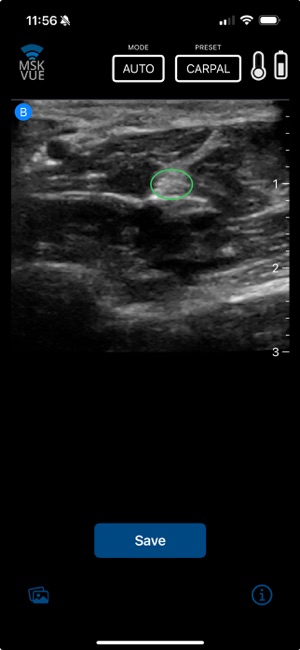

MSK VUE is a specialized training application for musculoskeletal ultrasound. The system utilizes an artificial intelligence component to support the identification of key peripheral anatomical structures within an interactive, simulated ultrasound imaging environment. The interface is designed to present visualizations of nerves, tendons, and bones, allowing users to engage with the simulated data. This application's core mechanism focuses on presenting specific anatomical targets and facilitating their recognition through its AI-driven framework, providing a platform for practice in a non-clinical context.